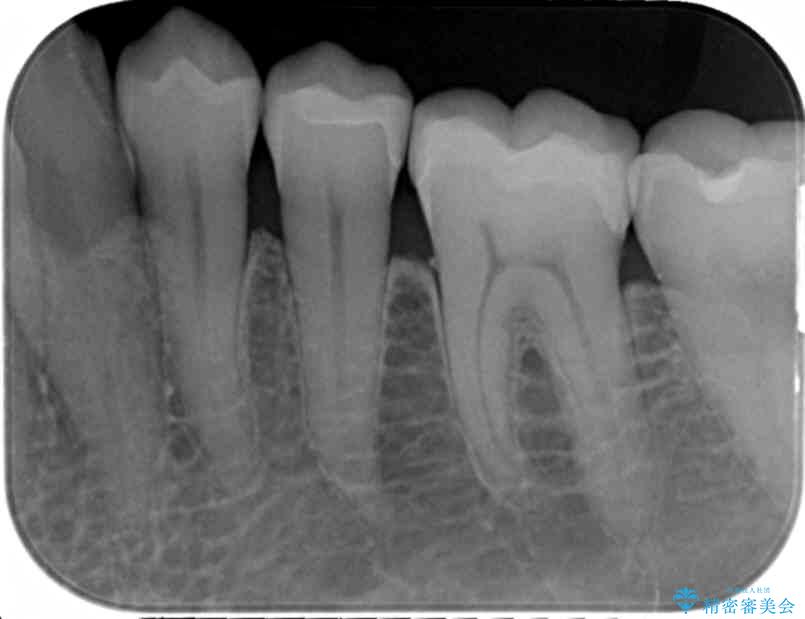

銀歯を丁寧に除去し、セラミクインレーによる置き換えを行いました。

セラミックインレーの治療に際しては、拡大鏡を用いた丁寧な除去・形成、シリコン印象材による精密な型取りを行い、虫歯の再発を防ぐような精密修復を実践していきます。